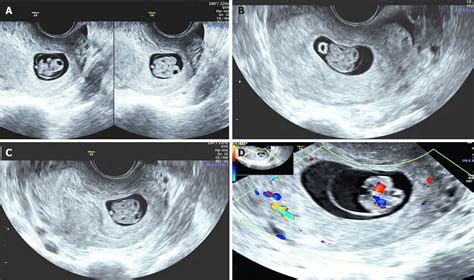

• Transvaginal Ultrasound: At 6 weeks, a transvaginal ultrasound is often used because it provides a clearer image of the uterus and the developing embryos. This procedure involves inserting a small probe into the vagina, which emits sound waves to create images of the uterus.

• Detection of Gestational Sacs: The primary goal of the 6 week sonogram twins is to detect the presence of two gestational sacs. Each sac contains an embryo and will eventually develop into an amniotic sac.

• Heartbeat Detection: While it is possible to detect fetal heartbeats at 6 weeks, it is not always guaranteed. The heartbeats may be visible as flickering movements within the gestational sacs.

• Measurement of Embryos: The ultrasound technician will measure the size of the embryos to ensure they are developing at the expected rate. This measurement is crucial for assessing the health and viability of the twins.

• Presence of Gestational Sacs: The detection of two gestational sacs confirms a twin pregnancy. This is a crucial finding that sets the stage for ongoing monitoring and care.

• Fetal Heartbeats: If fetal heartbeats are detected, it is a positive sign of viability. However, the absence of heartbeats at this stage does not necessarily indicate a problem, as it may be too early to detect them.

• Embryo Measurements: The size of the embryos will be measured to ensure they are developing at the expected rate. Any discrepancies may require further monitoring or additional tests.